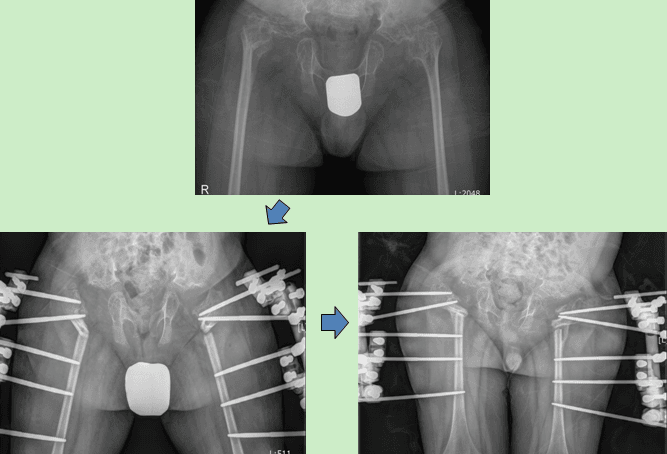

Notice: Hip Correction in a Patient with Spondyloepiphyseal Dysplasia

척추골단이형성증 환자로 보행이 불편하고 척추기 휘어 고관절 교정술을 시행하였습니다.

Hip joint correction was performed on the patient with spondyloepiphyseal dysplasia due to difficulties in walking and deformed spine.